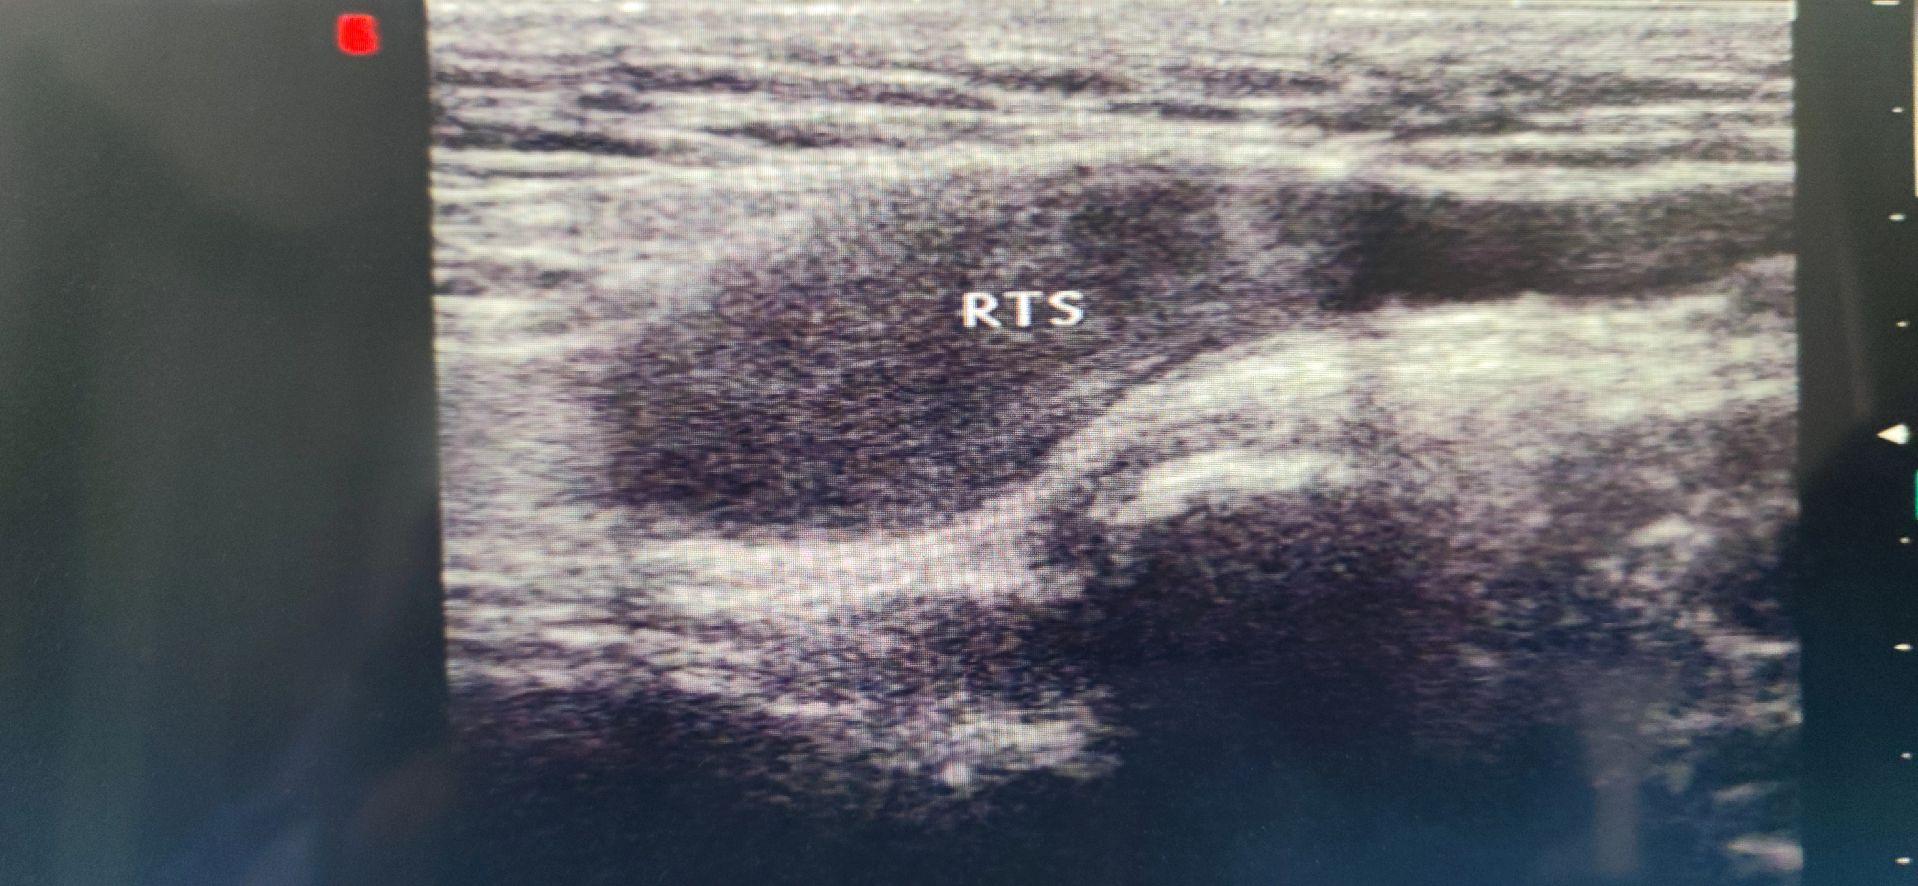

隐睾。右侧腹股沟区见睾丸,可以移动至膀胱右侧